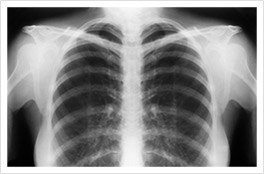

X-Ray scan of someone's chest.

X-Ray

X-ray scans can show abnormalities in the body, such as fluid buildup or masses.

X-rays are mesothelioma imaging scans that offer a fast, low-dose way to look for problems in the chest. Doctors use them to spot fluid around the lungs, areas of unusual thickening or a collapsed lung that may signal pleural disease.

Doctors check for warning signs linked to mesothelioma, like pleural effusion, pleural thickening, or a partly collapsed lung. X-rays can miss small or early tumors, and they do not diagnose cancer alone. If your X-ray raises concern, your doctor will order advanced scans and, if needed, a biopsy to be sure.

On a chest X-ray, pleural or pericardial mesothelioma tumors appear as wispy white areas around the lungs, while calcified tumors appear bright white. Bones appear white and healthy lungs are dark. Most abnormalities appear as lighter areas that are hazy or solid.

Tumors and scarring may distort chest anatomy. Compressed lungs or a raised diaphragm can be visible on an X-ray.

X-rays are 2D, making it hard to determine if a tumor is in the lung, pleura or the mediastinum around the heart. Additionally, X-rays don’t clearly show peritoneal or testicular mesothelioma. CT, MRI and PET/CT scans offer more detailed images for all mesothelioma types.